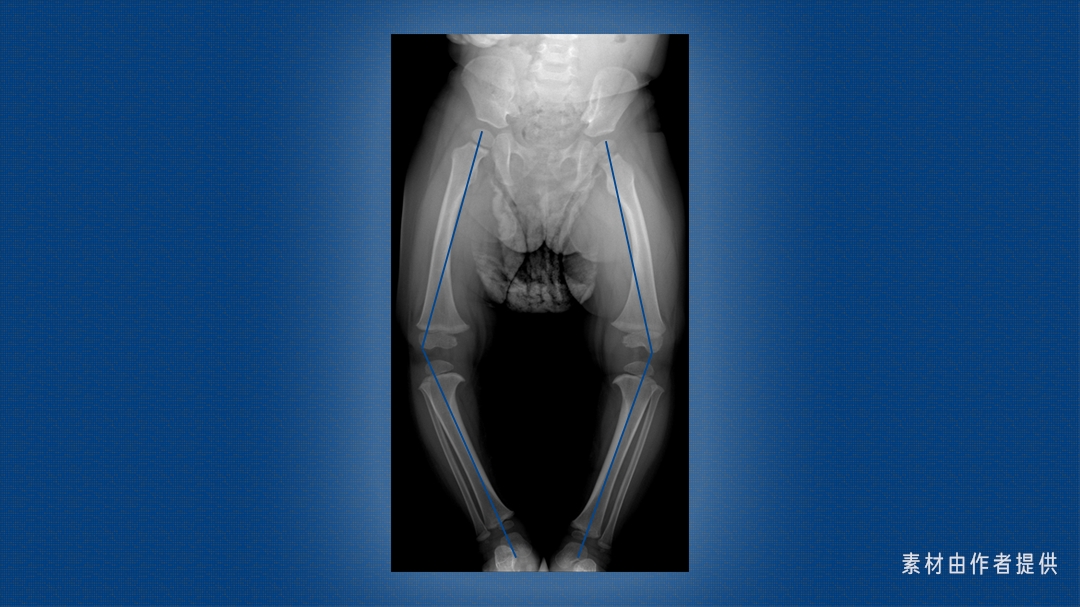

这是一双 O 型腿,也叫「膝内翻」,大腿和小腿轴线的交点偏离身体中轴线。

这个角度一般用胫股角来衡量,也就是大腿和小腿的轴线在膝关节处的夹角,其数值随年龄发生特征性变化。